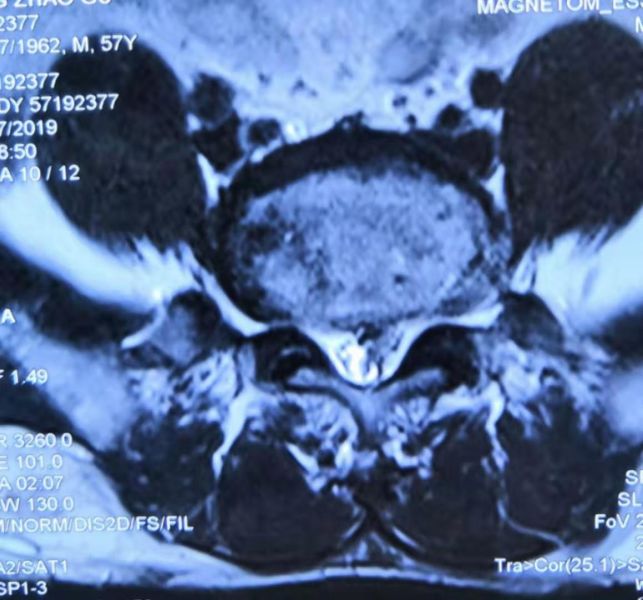

术前L4/5椎间盘脱出

术前 L4/5

椎间盘脱垂